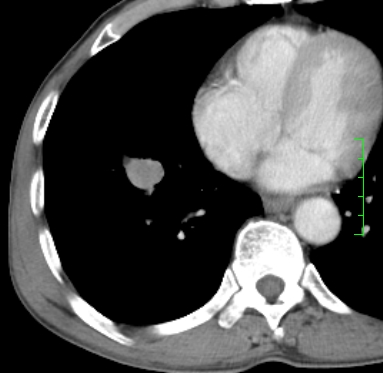

m,73y。膝关节疼痛伴双下肢水肿。入院常规胸片发现结节灶。增强为静脉期。

指套征,强化明显,近侧肺组织局限性肺气肿,考虑支气管类癌,慢支、肺气肿、双上陈旧性tb、冠脉钙化。

1)考虑右肺下叶周围型肺癌。2)右肺上叶及左肺感染性病变(结核可能)。3)肺气肿。4)冠状动脉钙化。